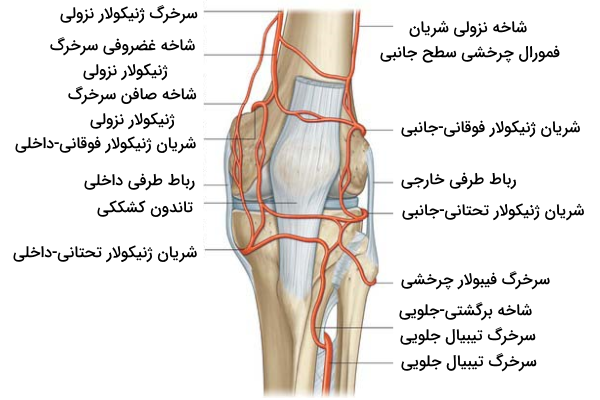

خونرسانی به زانو

مفصل زانو دارای شبکهای از رگهای خونی است که از « ژنیکولار آناستوموز» (Genicular Anastomosis) که به وسیله چندین سرخرگ شکل گرفته است، تامین میشود. رگهای اصلی خونرسان به این شبکه مواردی هستند که در ادامه نام میبریم.

- «سرخرگ رانی» یا «شریان فمورال» (Femoral Artery)

- «سرخرگ پشتزانویی» یا «شریال پوپلیتئال» (Popliteal Artery)

با وجود آن که این دو سرخرگ در خونرسانی به زانو از اهمیت زیادی برخوردار هستند، اما در مجموع ده سرخرگ در تشکیل ژنیکولار آناستوموز نقش دارند که آنها را میتوان در سه گروه شاخه نزولی، شاخه صعودی و شاخههای سرخرگ پشت زانویی گروهبندی کرد. در ادامه به کمک یک جدول با رگهای موجود در هر گروه آشنا میشویم.

| سرخرگهای سازنده ژنیکولار آناستوموز | |

| شاخههای نزولی | «شاخه نزولی شریان فمورال چرخشی سطح جانبی» (Descending Branch Of The Lateral Circumflex Femoral Artery) |

| «شاخه ژنیکولار نزولی شریان فمورال» (Descending Genicular Branch Of the Femoral Artery) | |

| شاخههای صعودی | «شاخه چرخشی فیبولار سرخرگ تیبیال پشتی» (Circumflex Fibular Branch Of The Posterior Tibial Artery) |

| «شاخههای برگشتی پشتی و جلویی منشعب شده از شریان تیبیال جلویی» (Anterior And Posterior Tibial Recurrent Branches Of The Anterior Tibial Artery) | |

| شاخههای سرخرگ پشت زانویی | «شریانهای ژنیکولار فوقانی جانبی و داخلی» (Lateral And Medial Superior Genicular Arteries) |

| «شریانهای ژنیکولار تحتانی جانبی و داخلی» (Lateral And Medial Inferior Genicular Arteries) | |

| «شریان ژنیکولار میانی» (Middle Genicular Artery) | |